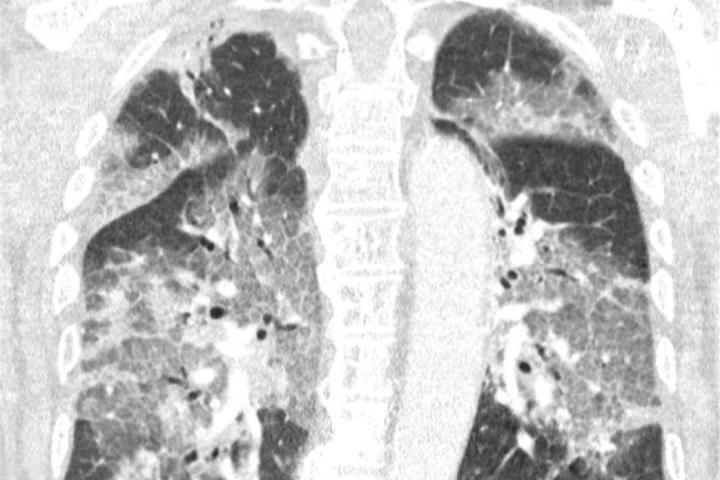

Imagen de los pulmones contagiados con coronavirus del hombre que rechazó la vacuna de AstraZeneca.EFE

“Hoy ingresó en nuestro hospital el primer paciente que se había negado a recibir la vacuna de AstraZeneca tras toda la conmoción en la prensa. Oímos el tremendo pesar en su voz y la desesperación en sus ojos. El virus lo ha atacado y podría haberse evitado. Con su permiso, compartimos su escáner de pulmón. No es necesario ser un especialista en pulmones para reconocer la devastación, ni epidemiólogo para explicar los riesgos de no estar vacunado”, alertaron.